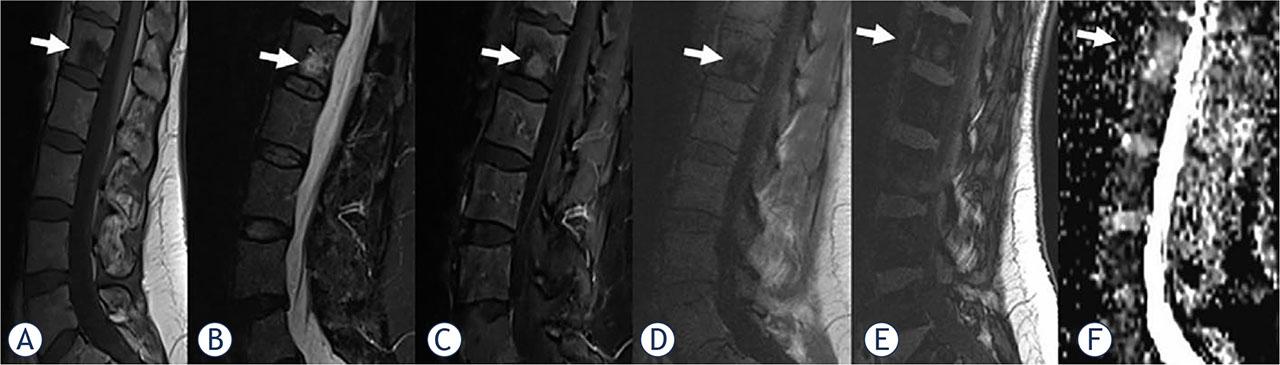

FIGURE 1.